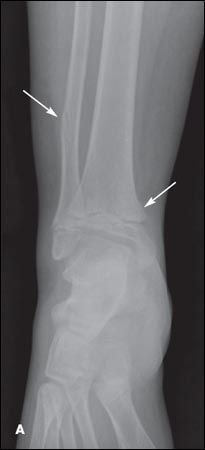

While playing on the school playground, a 10-year-old boy decided to try a zip line (Figure 1). He grabbed the pulley and slid down the cable. When the pulley came to a stop, he fell off and sustained a right ankle injury. In the emergency department (ED), the diagnosis was a right distal fibula shaft fracture and distal/medial Salter-Harris type II tibia fracture (Figure 2). The fractures were nondisplaced, and the child's right lower extremity was placed in a long leg cast, which was replaced 3 weeks later with a short walking cast; he was transitioned to a walker boot 2 weeks after that. The fractures healed without complications. Because of possible injury to the growth plate, follow-up in 6 to 9 months was needed to ensure there was no physeal arrest.

Figure 2 – Anteroposterior (

A

) and lateral (

B

) radiographs taken in the emergency department show a right distal fibula shaft fracture and distal/medial Salter-Harris type II tibia fracture.